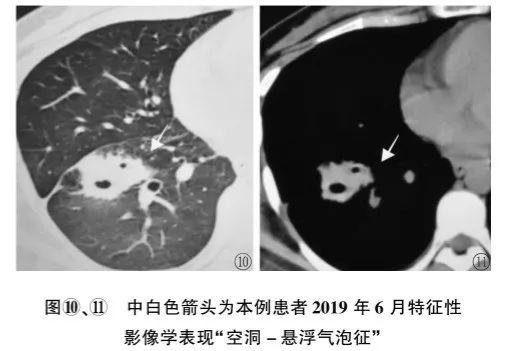

肺部空洞悬浮气泡征(图2),简单的说就是反常的存在,不把牛顿万有引力放在眼里(从表面上看):气体的分布与重力无关,不形成气液平,空气悬浮在液体里面。

图2 肺部空洞悬浮气泡征

图2 肺部空洞悬浮气泡征这个患者的病理是什么呢?

揭晓答案:放线菌感染(图3),空洞悬浮气泡征高度提示肺部放线菌病。

图3 放线菌感染

图3 放线菌感染图4也是肺部空洞悬浮气泡征,最终诊断也是肺部放线菌病。

图4 肺部空洞悬浮气泡征为什么肺放线菌病空洞内的空气会违反牛顿万有引力呢?有学者推测,对于肺放线菌病,空洞内低密度无强化的物质,其实是坏死组织+大量放线菌+硫磺颗粒,流动性差;空洞内的气体密度影,可能是含硫磺颗粒、放线菌的微脓肿,或是残存的扩张支气管。由此可见,空洞内的液体难以流动,气体也不容易流动,所以不会形成气液平。